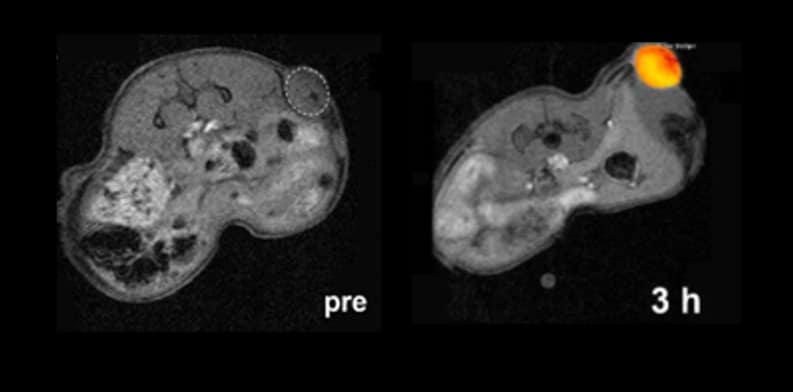

The final formulation was tested in vitro using 2D and 3D models of lung cancer, followed by evaluation in vivo using a mouse model of the disease. The results revealed a robust therapeutic activity comparable to that of the active drug, together with promising performance as MRI contrast agents.

“Manganese in its 2+ oxidation state is strongly paramagnetic, greatly enhancing its effect on the MRI signal, translating into clearer, brighter images”, adds J.Gallo. “Manganese dioxide nanoparticles, therefore, exhibit redox-responsive off/ON magnetic resonance behaviour, which can be explored for tumour detection and follow-up”.